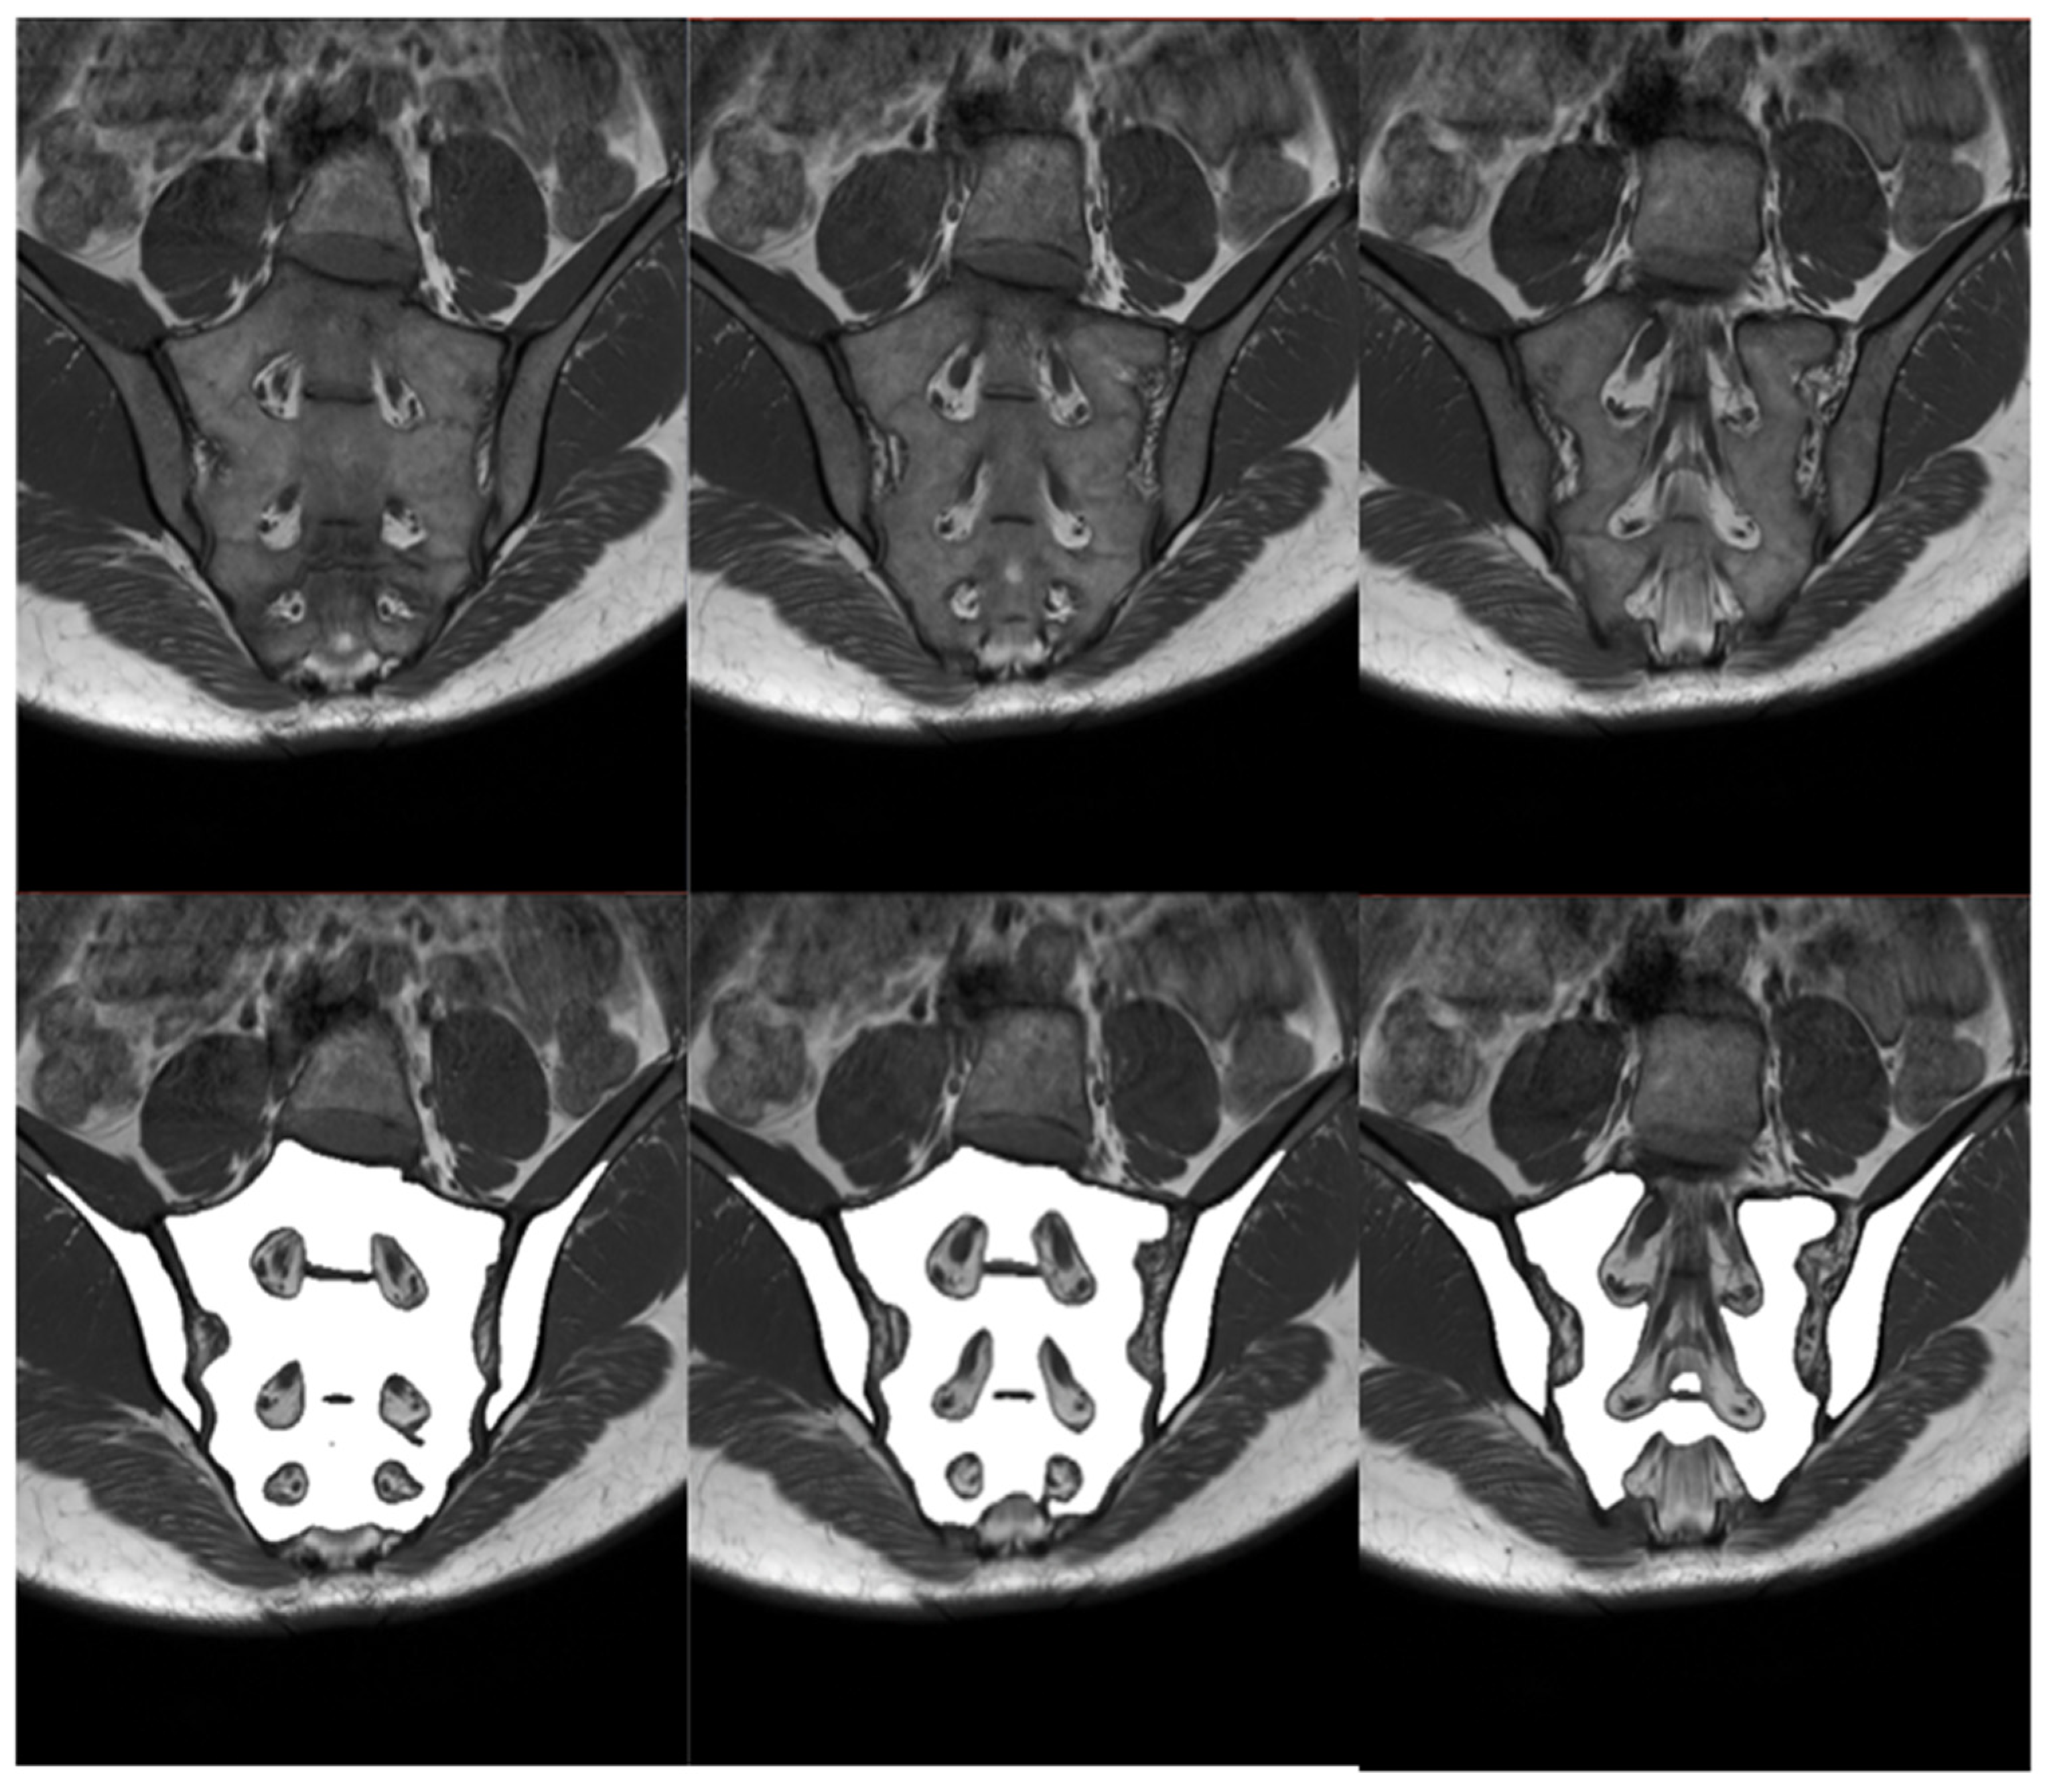

3.4. Manual and Automatic Segmentation of BME

The sample comparison of the performance of manual and automatic segmentations of BME is presented in Figure 8. The results of assessing the compatibility of manual and automatic BME segmentations with the visual scale described previously are provided in Table 4. Differences between the groups were checked using Kruskal–Wallis H test, which resulted in not being statistically significant, H(3) = 1.125, p = 0.7710. This outcome implies no difference in the algorithm’s performance in BME segmentation in relationship to the deviation angle. Due to the limitations of the SPARCC scale, the number of examinations which points were awarded (SPARCC > 0, n = 68) differs from the number of examinations with BME recognized when preparing manual segmentations (n = 83).

Figure 8.

Sample slices with inflammatory lesions (SPARCC = 17): STIR sequence in the upper row, manual segmentation in the middle row and automated segmentation in the lower row.